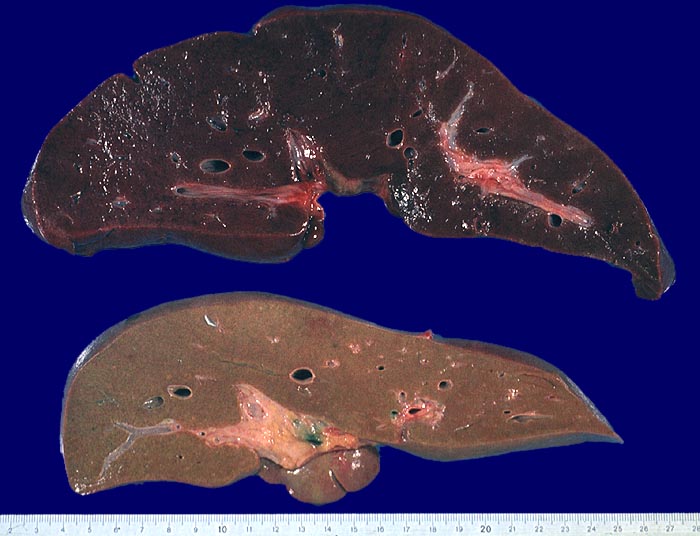

Makroskopie

Pathologischer Befund

Normalbefund